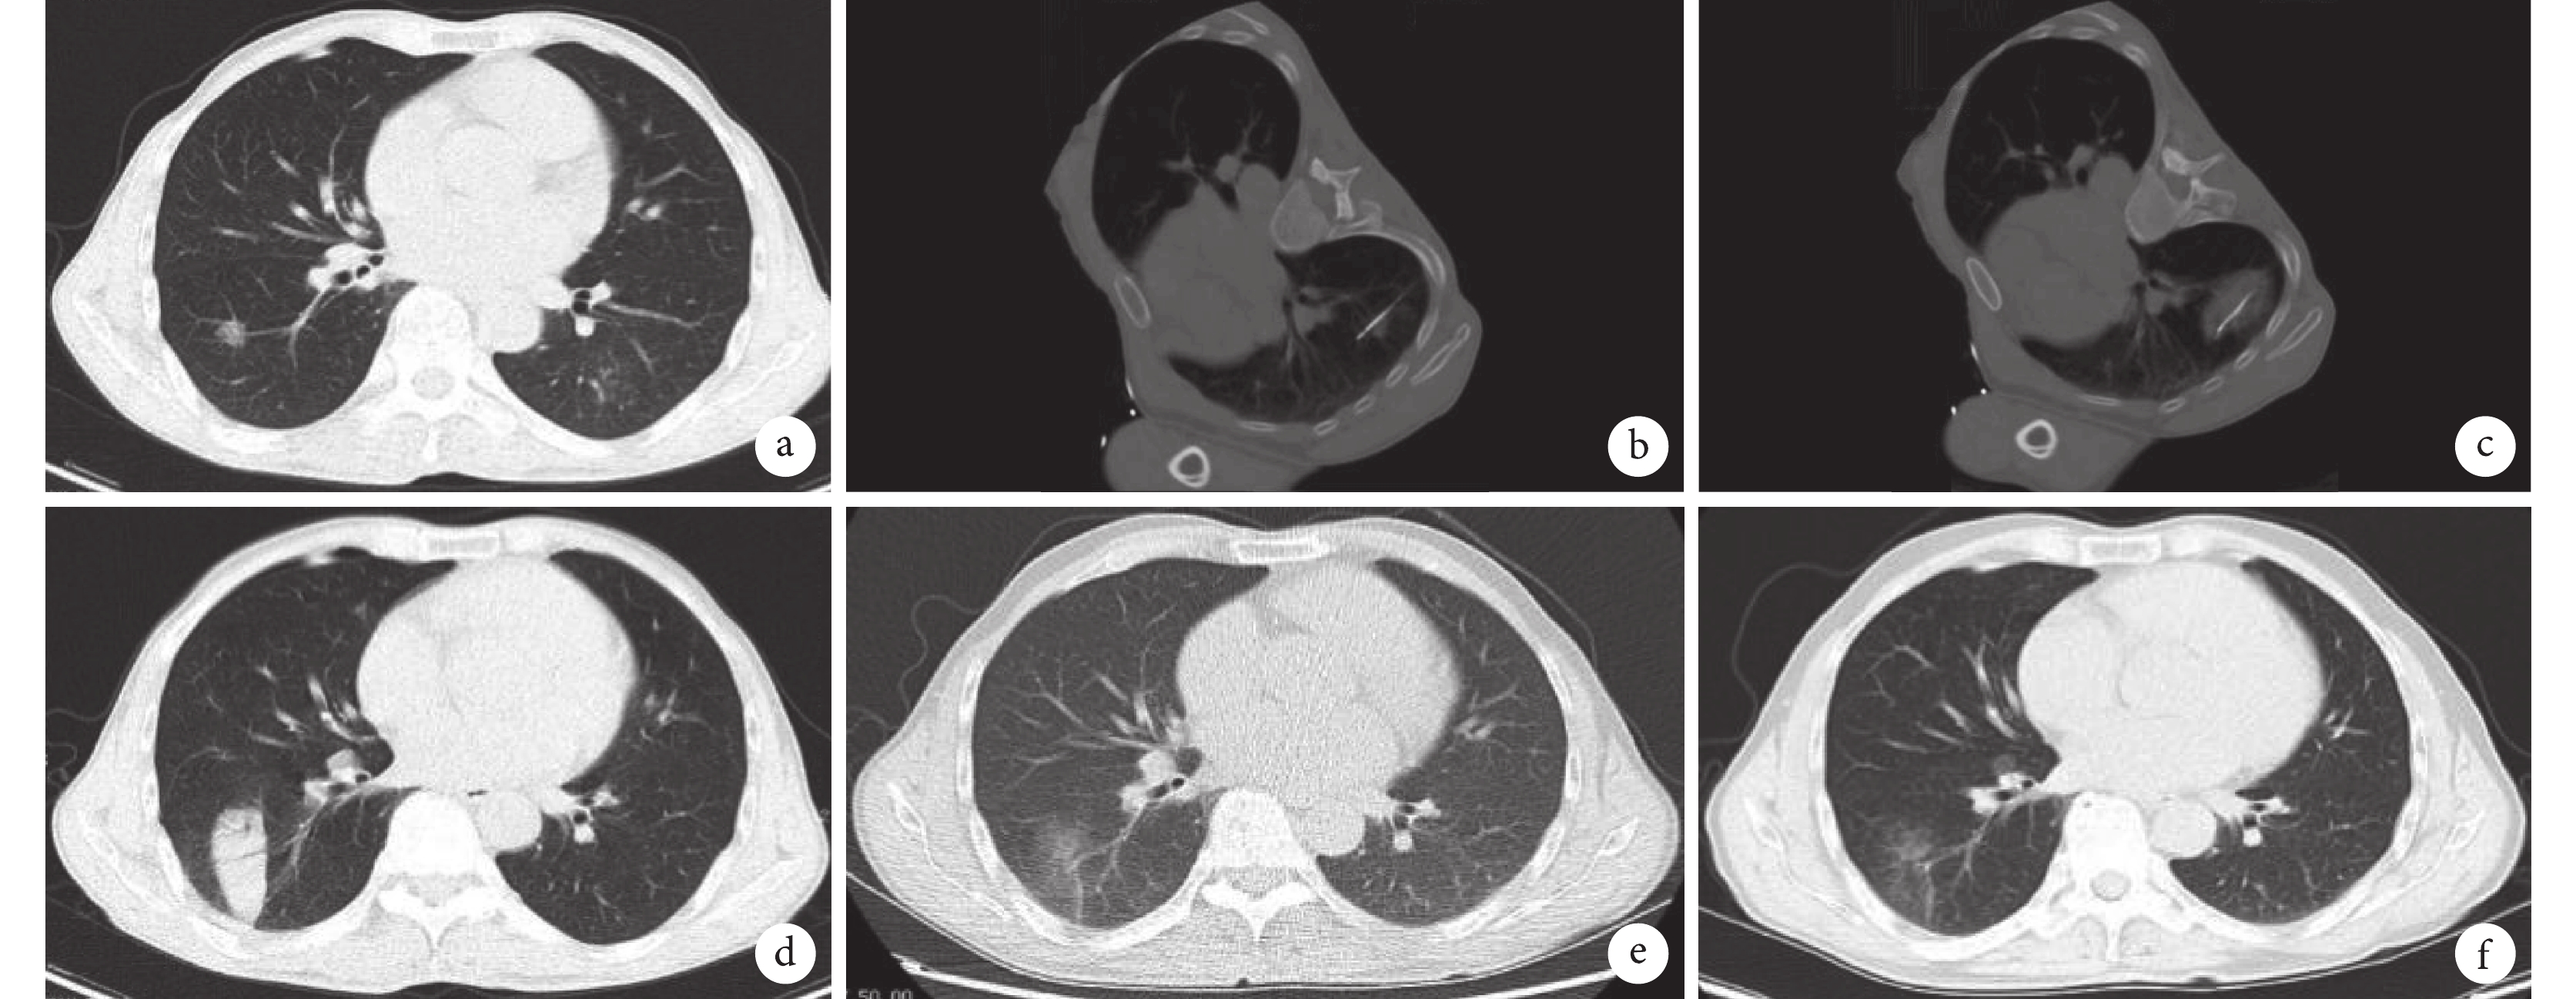

患者男,57歲,右下肺腺癌IA期T1bN0M0氬氦刀治療后病灶完全緩解。a. 治療前CT示右肺下葉結節,最大徑1.3 cm;b. 氬氦刀治療針置入病灶;c. 氬氦刀治療肺部結節,術中可見冰球形成;d. 氬氦刀治療1周后胸部CT示病變范圍明顯擴大;e. 氬氦刀治療后3個月病灶基本吸收,周圍部分滲出及纖維條索影;f. 氬氦刀治療23個月后,胸部CT示病灶完全吸收,殘留少量纖維條索影。